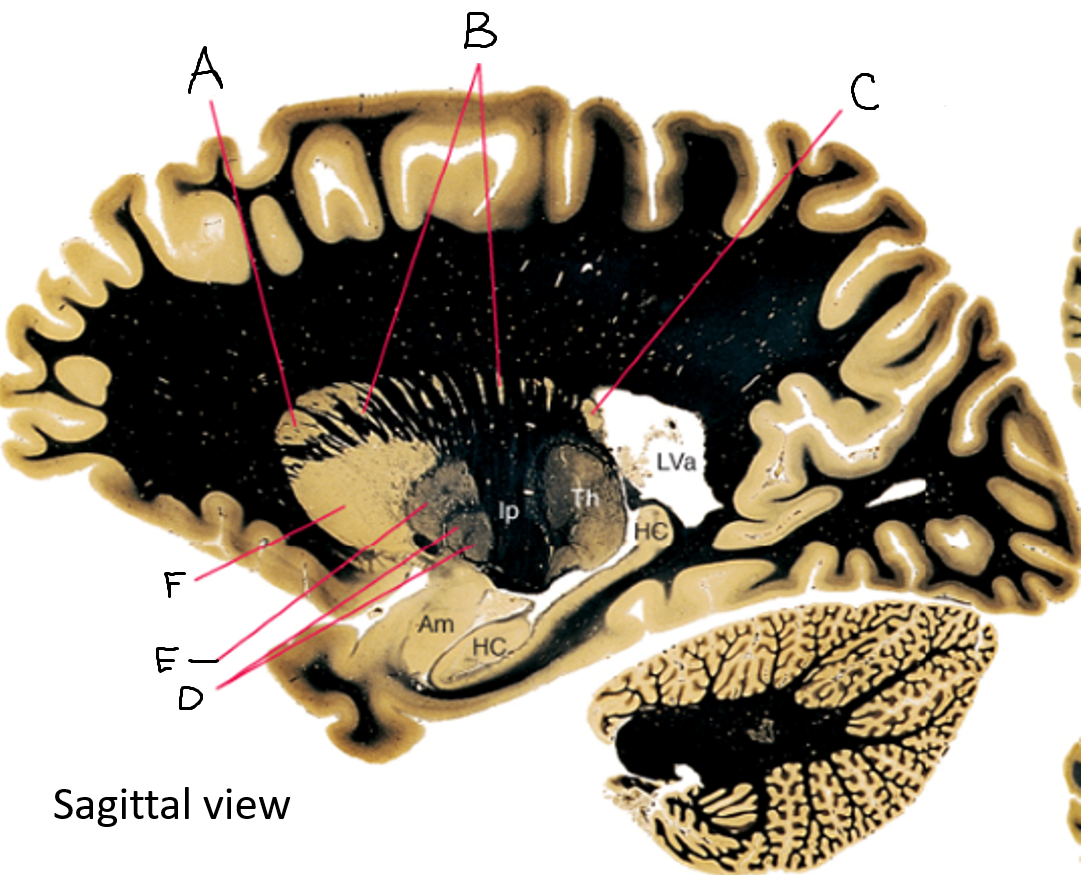

A

internal capsule (anterior limb)

B

caudate nucleus body

C

caudate nucleus head

D

putamen

E

caudate nucleus tail

F

thalamus

G

internal capsule (posterior limb)